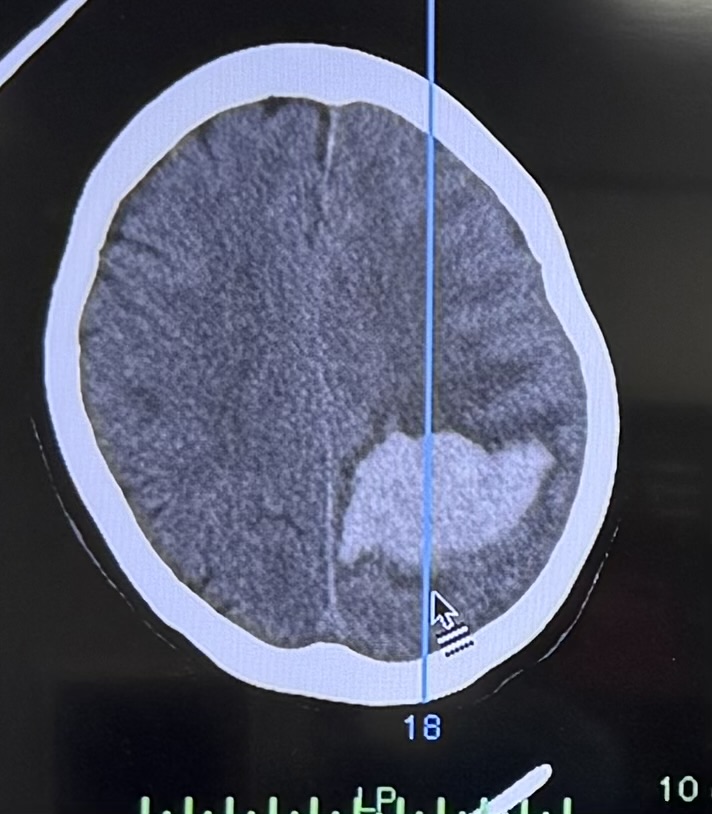

術後

画像は診療後に夜の緊急手術で内視鏡下血腫除去をした症例の写真です(局所麻酔、1時間で実施)。